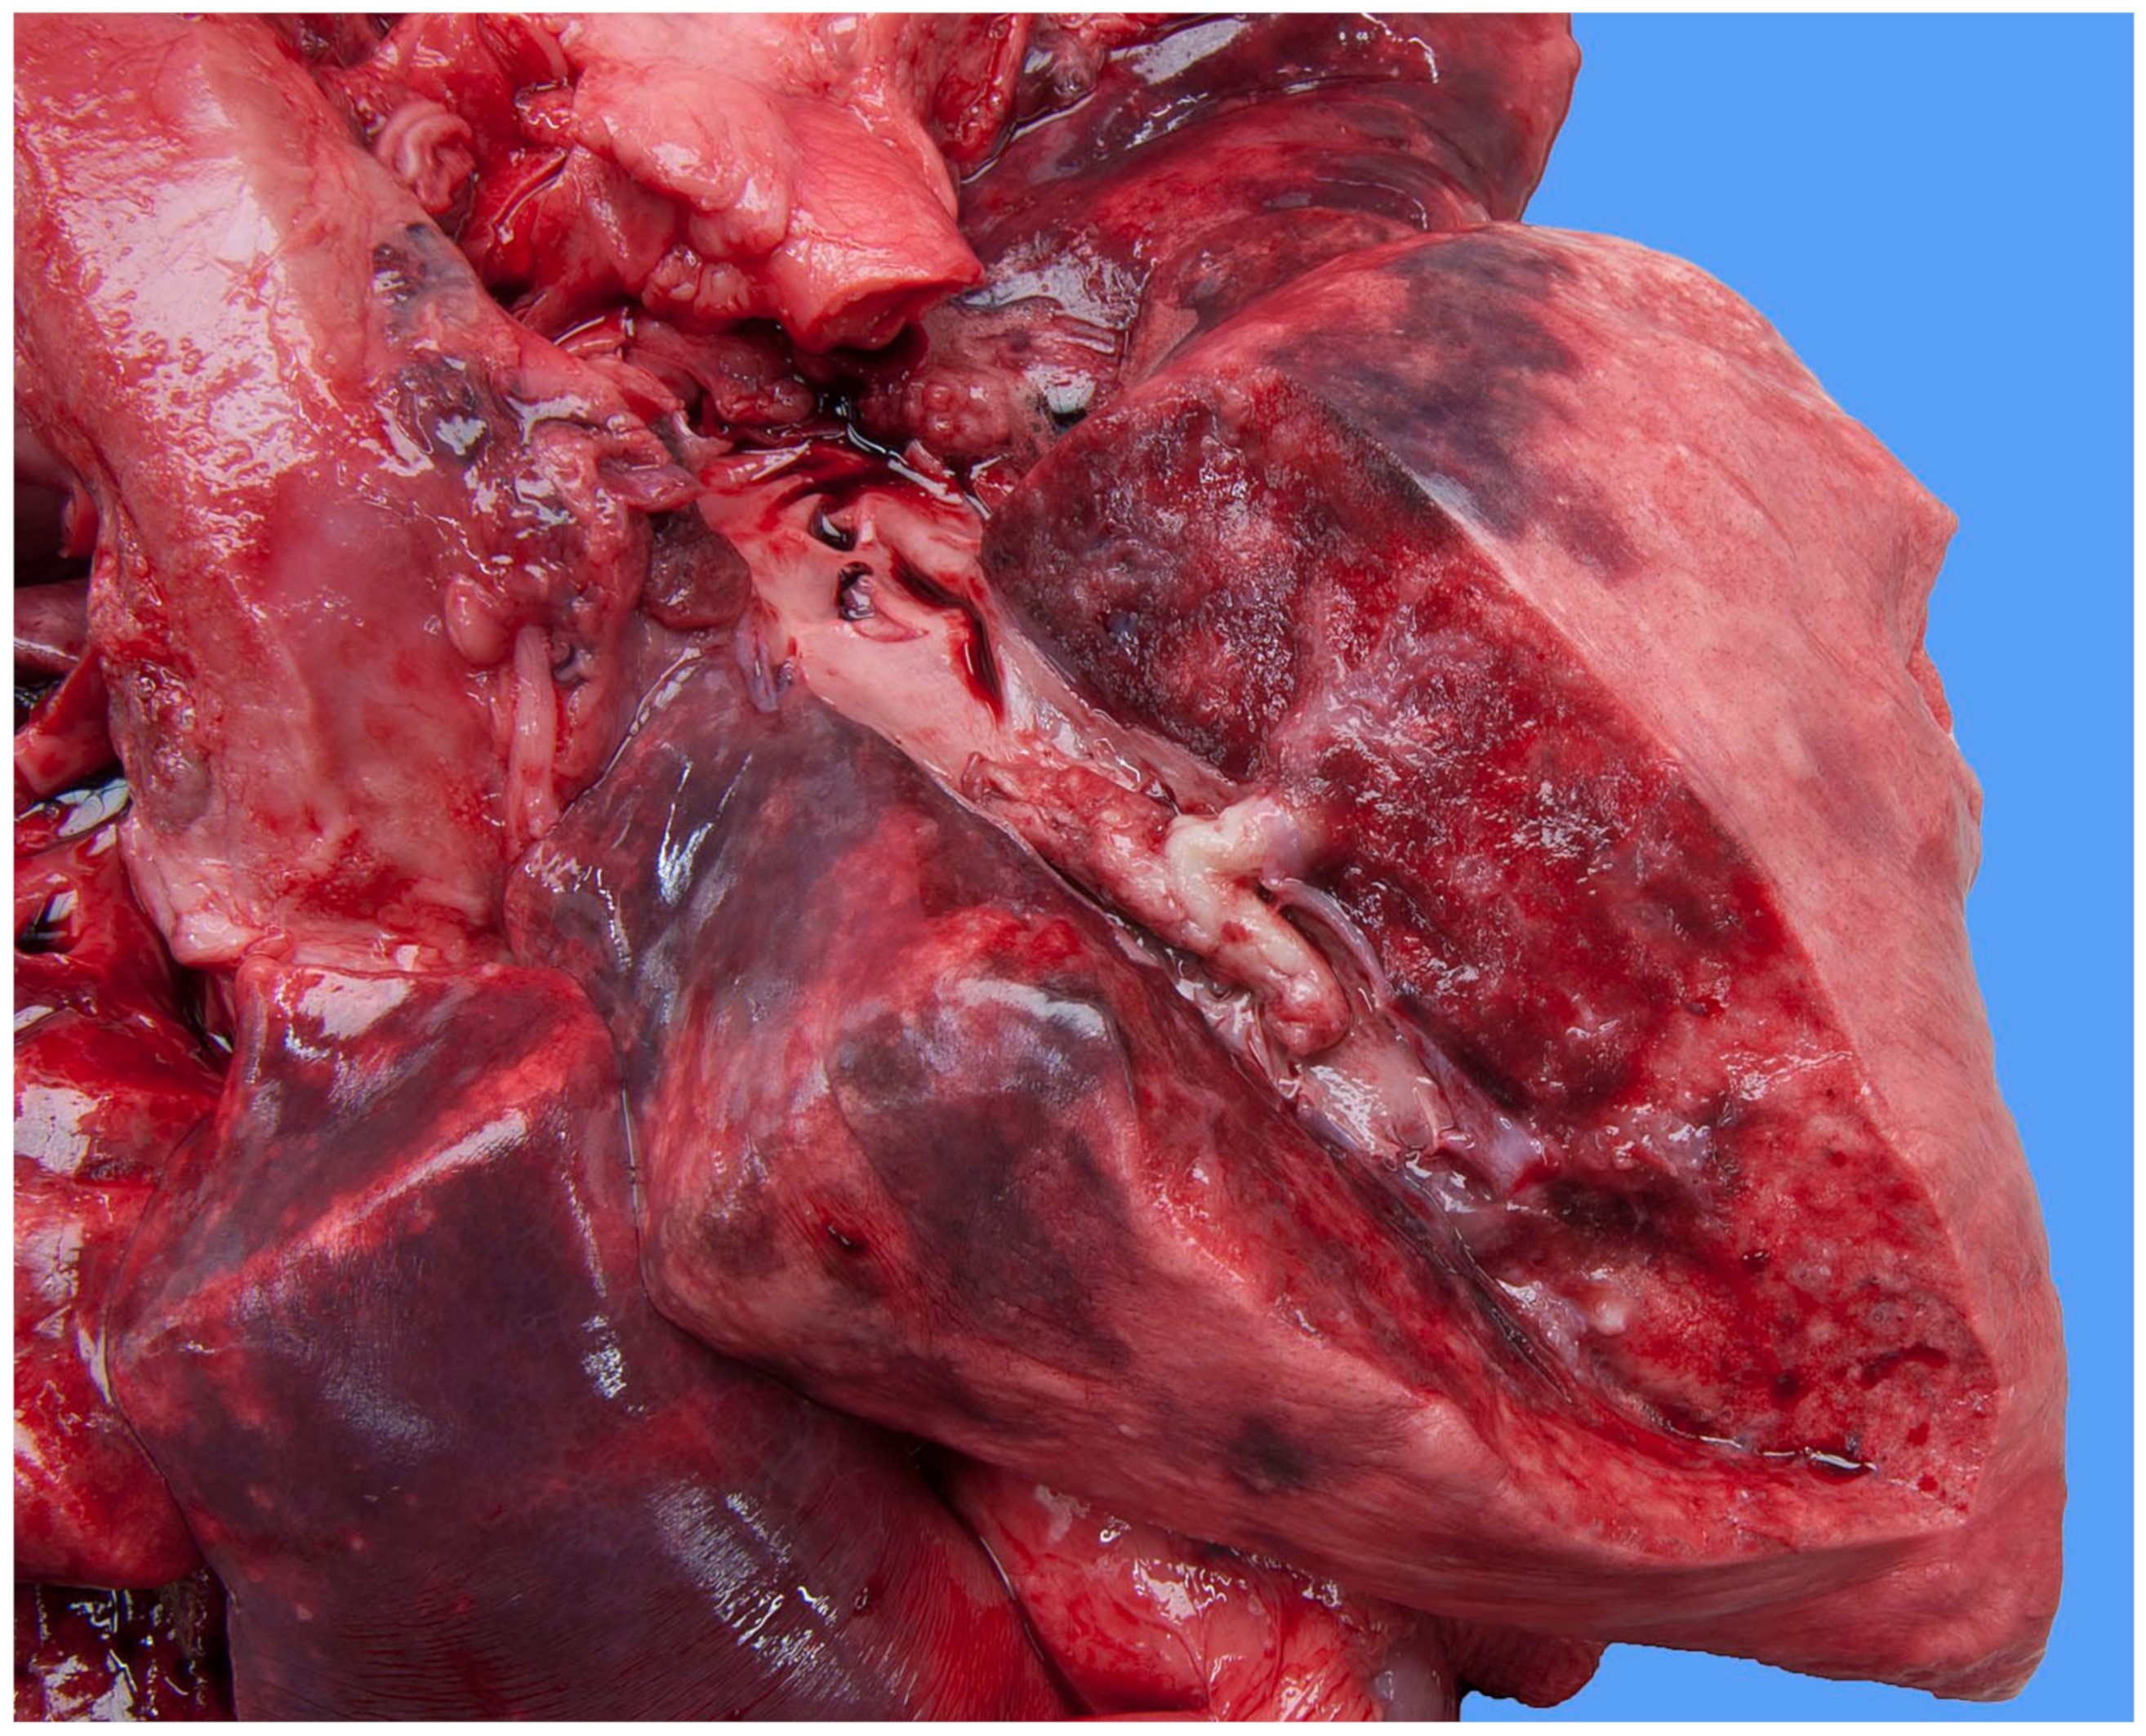

At necropsy, the pulse generator of the pacemaker was located subcutaneously in the right-sided intercostal space at the level of the fifth and sixth ribs. It was surrounded by a connective tissue capsule with no indication of inflammation in the adjacent tissue. The lumen of the right jugular vein was slightly dilated at the site of the entry of the electrode; there was no evidence of thrombus-forming.

Focally extending throughout the right ventricular lumen and partially incorporating the chordae tendineae and tricuspid valve leaflets, was a large (6 × 4 × 4 cm) thrombus adhered to the endocardium. A length of approximately 3 cm of the pacing electrode was embedded within the thrombus (Figure 7). The myocardium of the adjacent interventricular septum and free ventricular wall showed patchy white discoloration. The site of the tip of the electrode was visible in the apex as a small, slightly indented, firm, white area of connective tissue. Thrombus material filled the lumens of the right and left pulmonary arteries (Figure 8). The lungs were mildly congested and edematous. There was moderate congestion in the liver and mild ascites.

Figure 7.

Necropsy shows the right side of the heart and mediastinum of the dog. The walls of the jugular vein, the right atrium and the right ventricle are open allowing the visualization of the lumen. The pacemaker lead disappears in the pale soft tissue mass that fills the right ventricular chamber.

Figure 8.

Necropsy shows a large thrombus in the pulmonary artery of the right caudal lung lobe of the dog. The lung parenchyma has an edematous aspect.